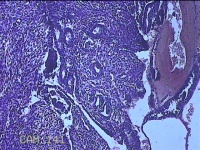

宫腔内容物

性别

女

年龄

43岁

临床诊断

异常子宫出血

一般病史

月经不规则2年余,发现宫颈赘生近1年,宫颈外科可见多个赘生物。

标本名称

大体所见

纱布一块,内有灰白暗红色不规则碎组织1.8x1.3x0.3cm一堆。